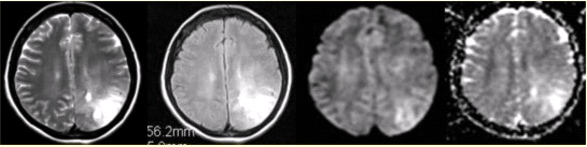

女性,42岁。癫痫1个月,近期加重。无发热,无其他病史。MRI表现如下图。 FSK_MN1_33.gif

• A.左侧顶叶不规则形长TXB2.gif信号影,边界清晰

• B.病变占位效应明显

• C.DWI和ADC显示病变均呈高信号,提示病变的TXB2.gif效应

• D.病变邻近蛛网膜下腔增宽

• E.病变邻近脑膜增厚